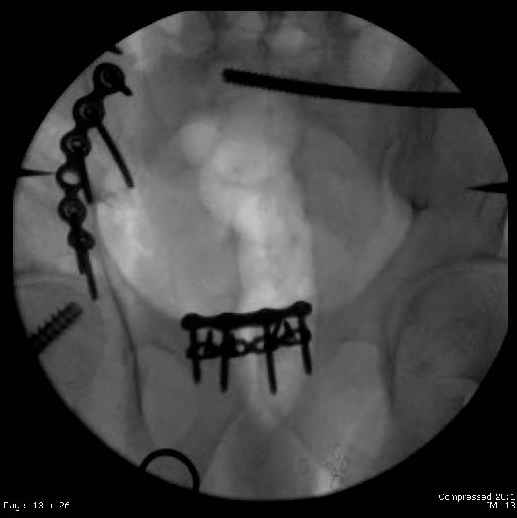

Here are the postop fluoros.

Fluoroed L SI joint and it seemed stable, but wide. So, applied c-clamp to try to squeeze down L SI joint (and note, on the last slide attached, that it's still wide), and got it closer. Single perc Iliosacral screw 40mm thread.

So, there I was with the aforementioned info on my mind, and my R iliac wing was a little malreduced. I think it's in residual extension and some external rotation, explaining the 5-6mm gap/step

on the posterior R iliac wing. (When I loooked at the inlet fluoro, the L obturator foramen was more visible than the R obt foramen, as was the R ischial spine) so it's not as stable as if it were

anatomic, despite all the metal. This came from hesitance to take down all the posterior paraspinals to really see the R posterior crest (where the malreduction is best seen on the iliac oblique view), and I could see the entire iliac fossa and most of the crest anyway.

Finally, the L SI joint seemed wide, even after closing it with c-clamp and iliosacral screw, so I added the extra 4 hole symphyseal plate anteriorly (even though to my knowledge unproven). That was the thinking and sequence of events that lead to the 2 symph plates shown. Note that the 4 hole recon is a locking plate (non-locked in medial 2 holes before locked screws in holes 1 & 4) -- fertile ground for debate on that I'm sure!